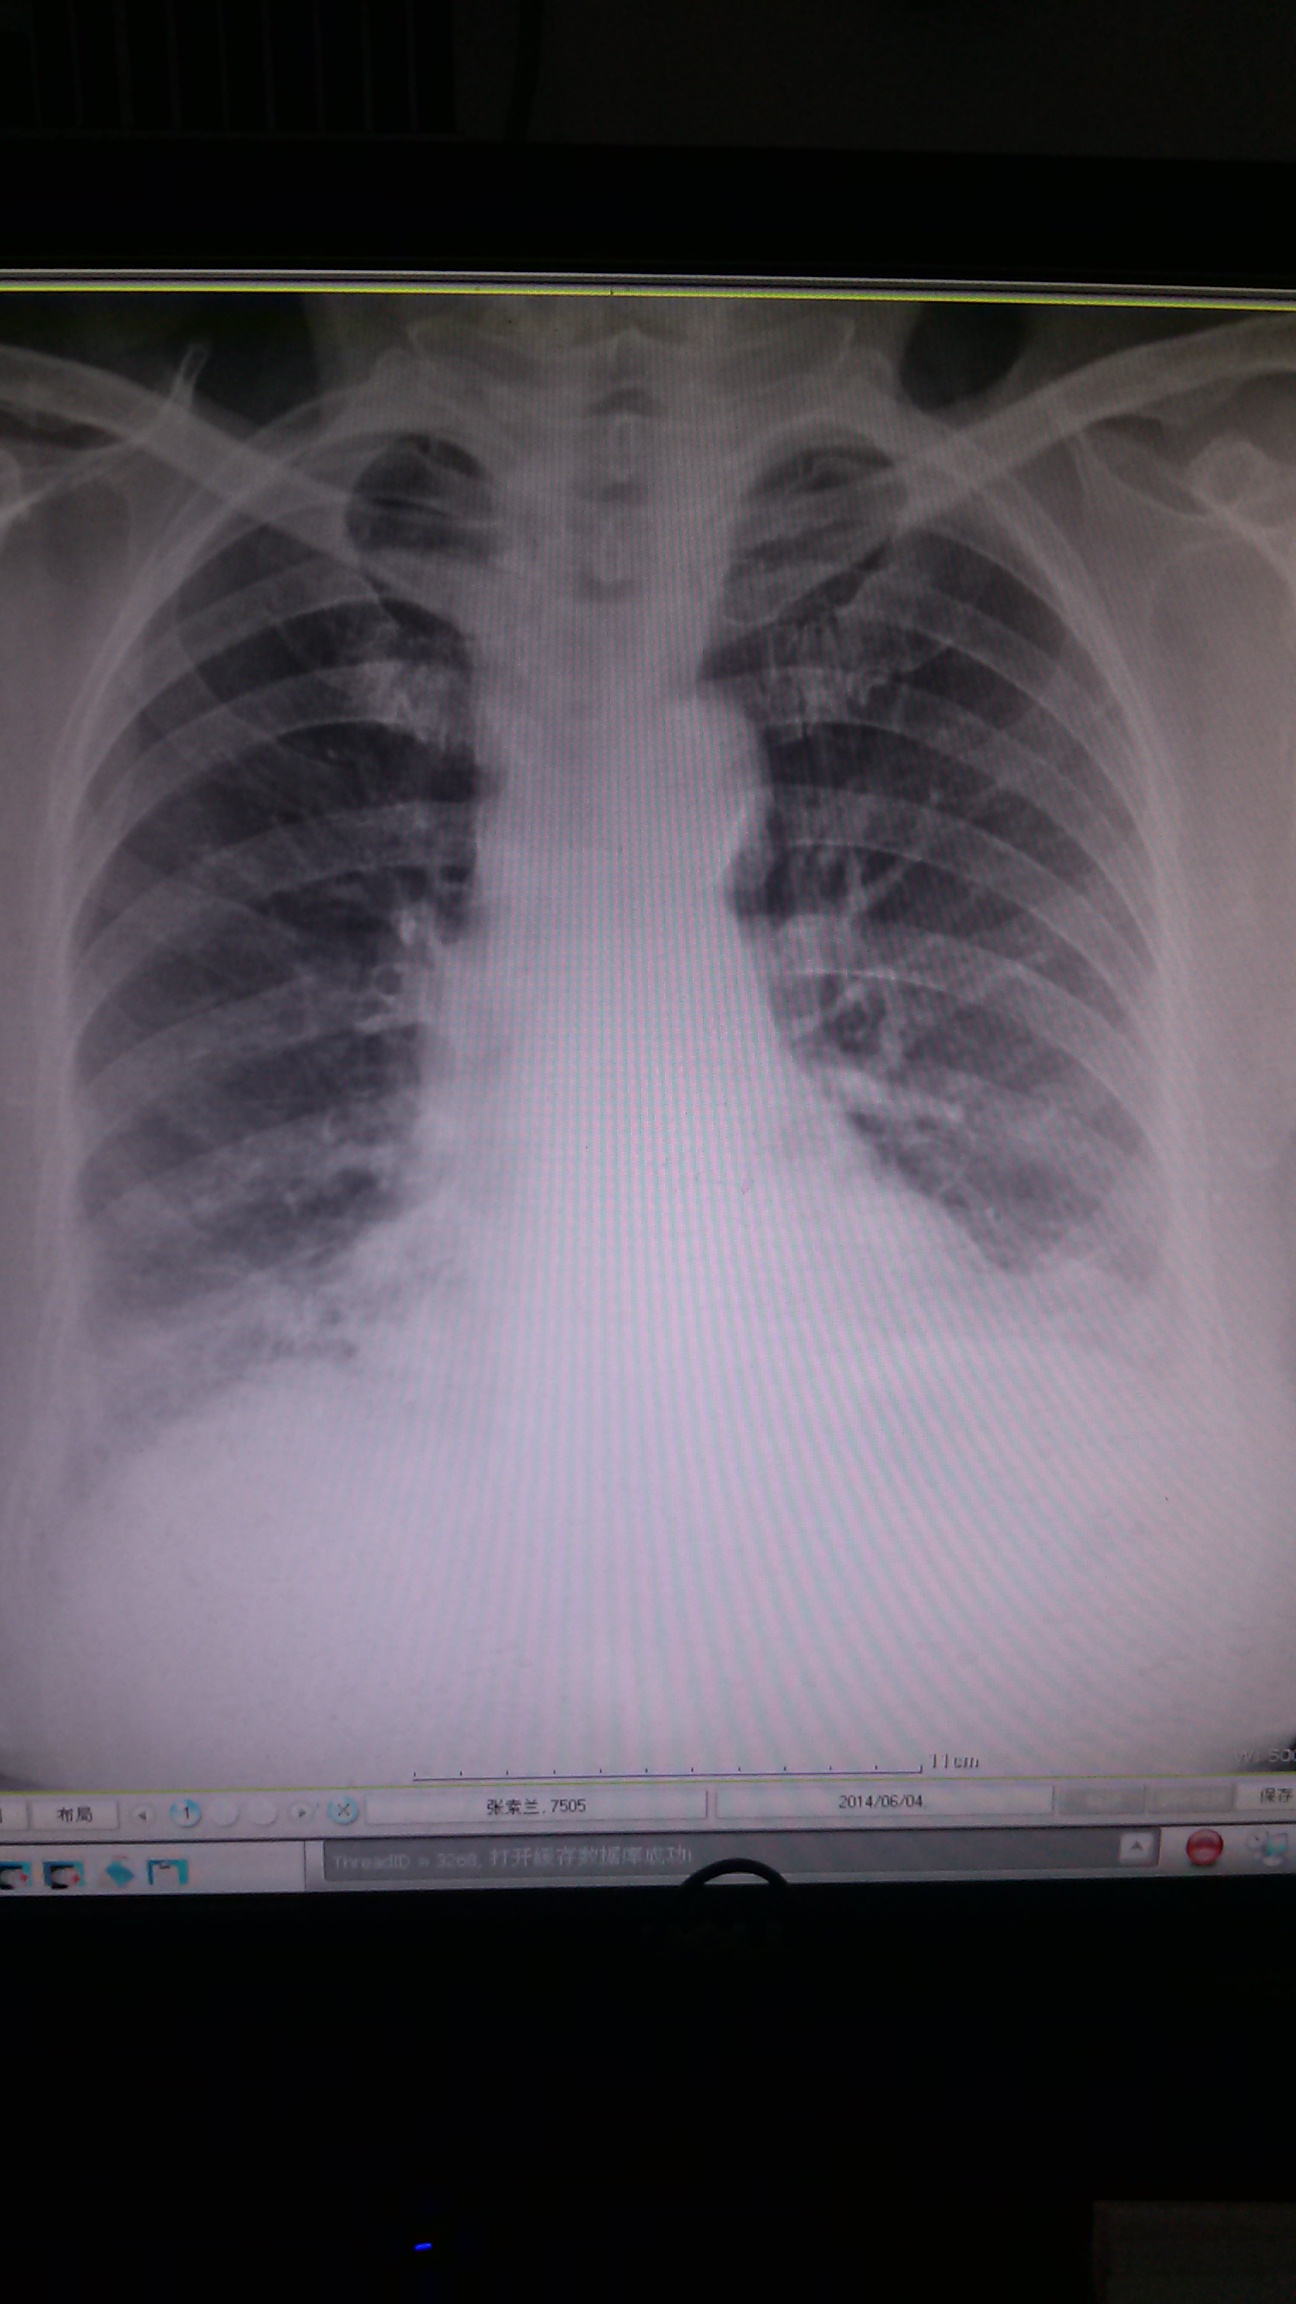

胸闷 76岁 女